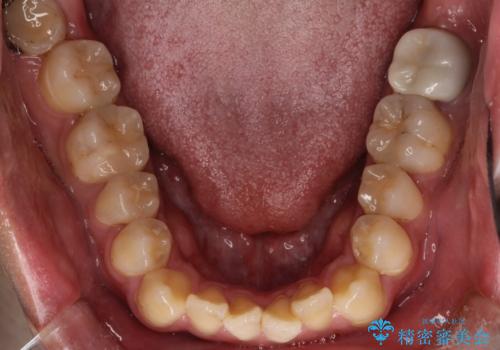

【ワイヤー矯正】前歯の凸凹を治したい。

- 前歯の凸凹を主訴に来院されました。

患者様がマウスピース矯正の使用時間に不安があるため、ワイヤー矯正にて治療を行なっております。